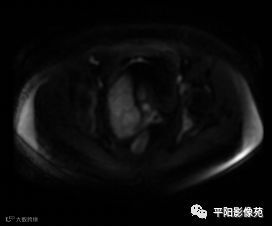

MRI表现

DWI轴位

(宫腔内见金属节育环伪影)宫颈区见不规则形等T1稍长T2信号软组织肿块,DWI序列呈明显高信号,大小约为3.87cmX2.64cm,双侧宫颈基质低信号环连续性中断,病灶向子宫右后上方生长,周围脂肪间隙模糊,增强扫描明显强化,强化程度低于子宫及宫颈实质;子宫后方、子宫直肠间隙见不规则形长T1长T2信号软组织肿块,DWI序列呈高信号,大小约10.12cmX4.82cmX10.29cm,病灶呈分叶状,向下方生长与宫颈分界不清,与直肠分界尚清,增强扫描明显不均匀强化。